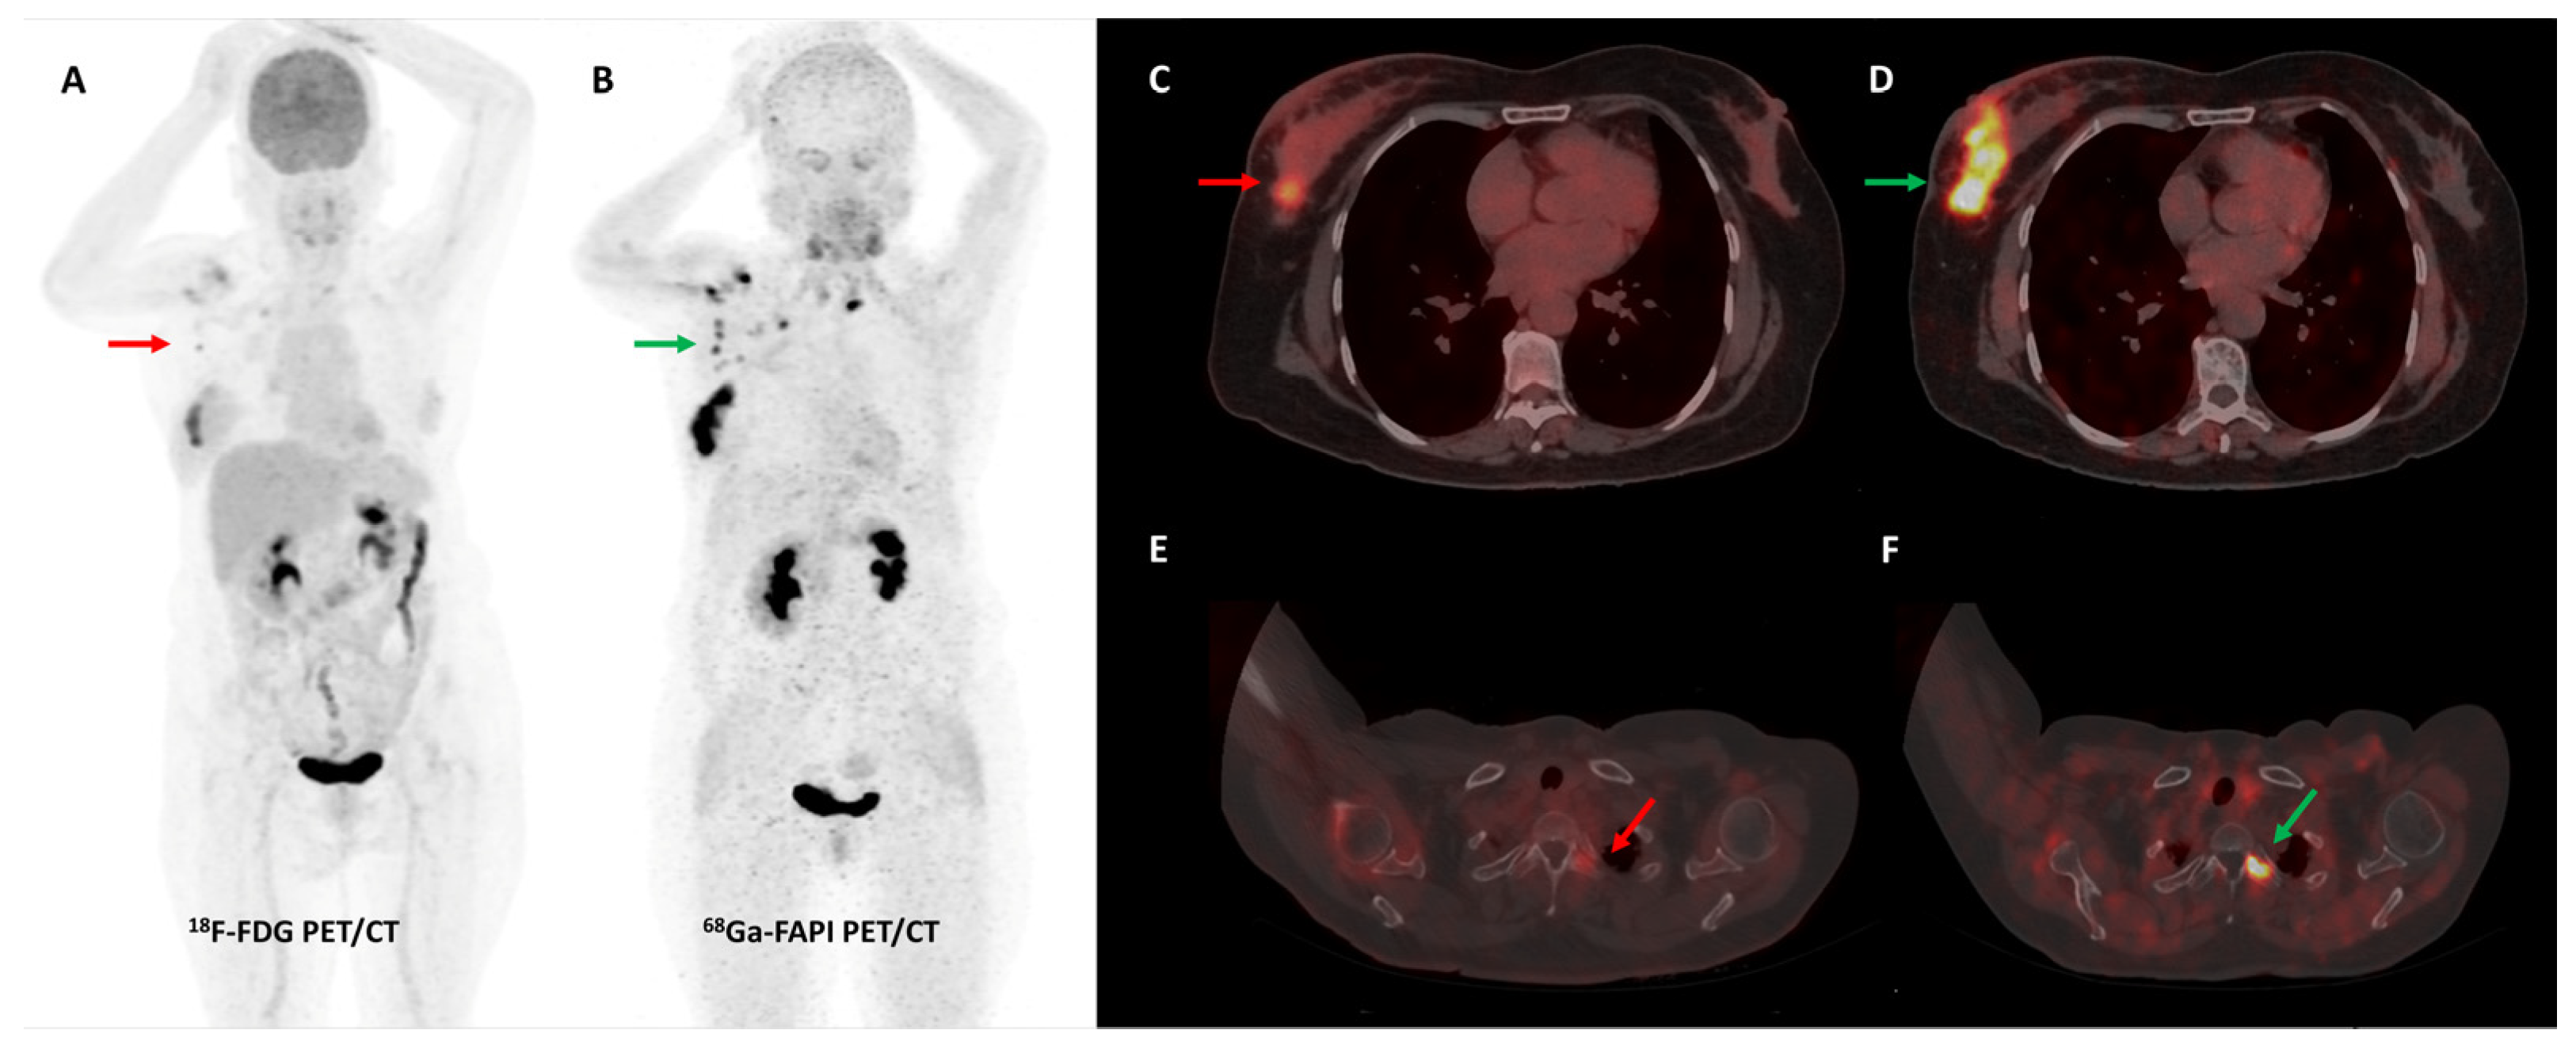

Loktev et al. conducted a proof-of-concept study in 2018 where they first demonstrated high lesional tracer uptake in three patients with breast, lung, and pancreatic cancers on FAPI PET imaging [24]. Subsequently, the same group from Heidelberg reported [68Ga]Ga-FAPI-04 PET/CT results of 80 patients with 28 different tumor types. The degree of tracer uptake differed significantly among tumor types, being highest in sarcoma, cholangiocarcinoma, esophageal, breast, and lung cancer [51]. Few other basket trials evaluated FAPI PET/CT in heterogeneous, oncological patient cohorts. The most consistent advantage of FAPI over FDG across these studies was easier lesion detection owing to a significantly lower background signal, with resultant higher target-to-background ratios (TBRs) and sharp image contrast [52]. One such example is presented in Figure 2.

Figure 2.

[68Ga]Ga-FAPI-04 and FDG PET/CT images in a 59-year-old woman with biopsy-proven metastatic left lung adenocarcinoma. [68Ga]Ga-FAPI-04 PET/CT images revealed intensely tracer avid left hilar mass lesion ((B)—green arrow), multiple enlarged mediastinal ((A,C)—green arrows) lymph nodes, and bilateral adrenal metastases ((A,D)—green arrows depicting left adrenal lesion). Additionally, moderate left-sided pleural effusion with associated left lung lower lobe collapse was noted. Overall, FAPI PET/CT demonstrated higher tracer avidity and TBRs than FDG PET/CT ((E–H)—red arrows).